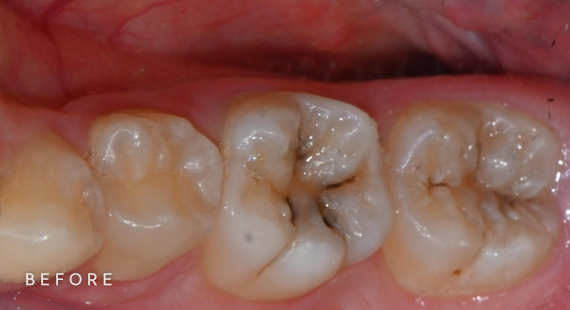

충치치료